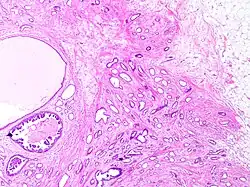

Tubular carcinoma

Tubular carcinoma is a subtype of invasive ductal carcinoma of the breast.[2][3] More rarely, tubular carcinomas may arise in the pancreas[4] or kidney.[5] Most tubular carcinomas begin in the milk duct of the breast and spread to healthy tissue around it.[6][7]

Although tubular carcinoma has been considered a special-type tumor,[a] recent trend has been to classify it as a low-grade, invasive NOS carcinoma because there is a continuous spectrum from pure tubular carcinomas to mixed NOS[b] carcinomas with tubular features, depending on the percentage of the lesion that displays tubular features.[10]: 647

Tubular carcinomas are generally around 1 cm. or smaller, and are made up of tubules. They are usually low-grade.[2] Elastosis has been noted as common but is not present in all cases.[11]

A highly differentiated invasive carcinoma that forms well-defined tubules (containing epithelium, but no myoepithelium) and that have abundant desmoplastic fibrous stromal reaction between the tubules.